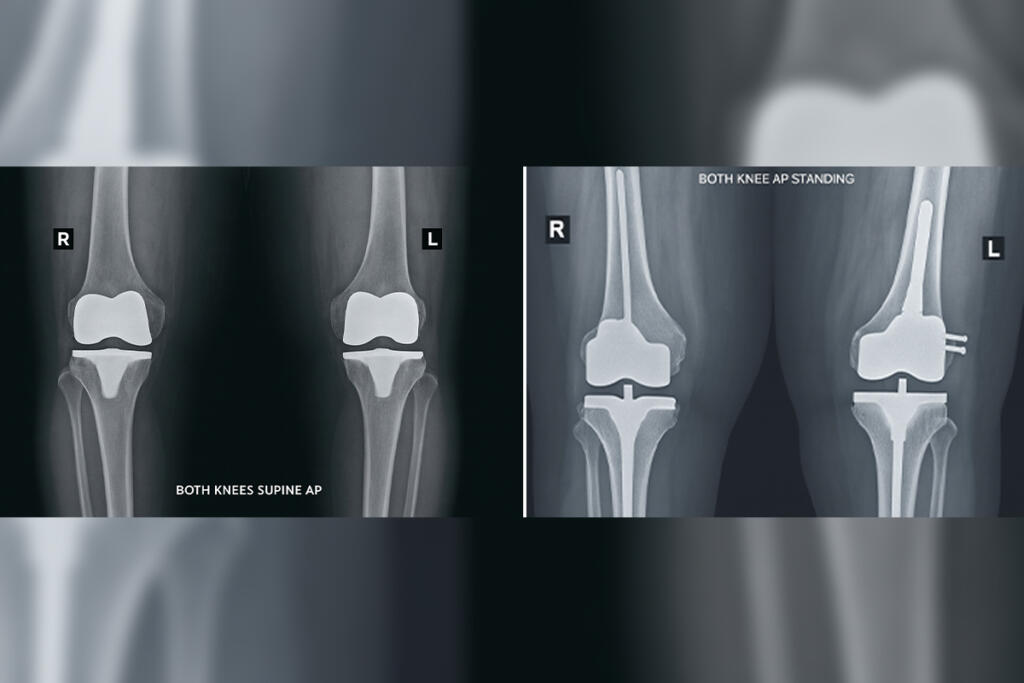

Primary Knee Replacement

Revision Knee Replacement

Revision Knee Replacement is a surgical procedure to replace a previously implanted artificial knee joint that has worn out or failed...